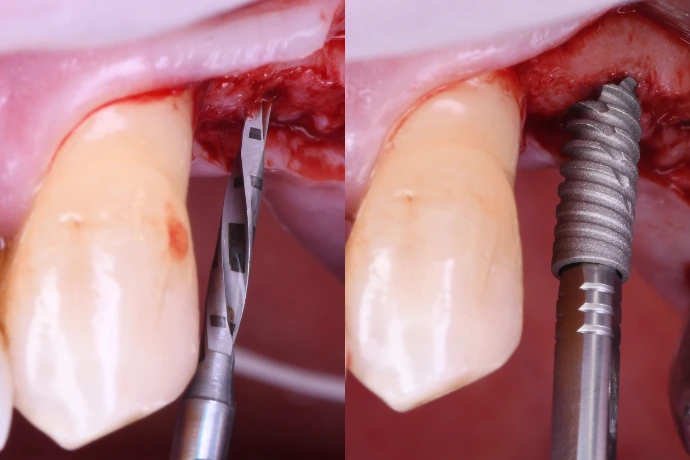

Préservation alvéolaire, régénération osseuse simple et optimisation mucogingivale.

TP : lambeaux, greffes conjonctives et épithélio-conjonctives sur mâchoires animales, ROG péri-implantaire.